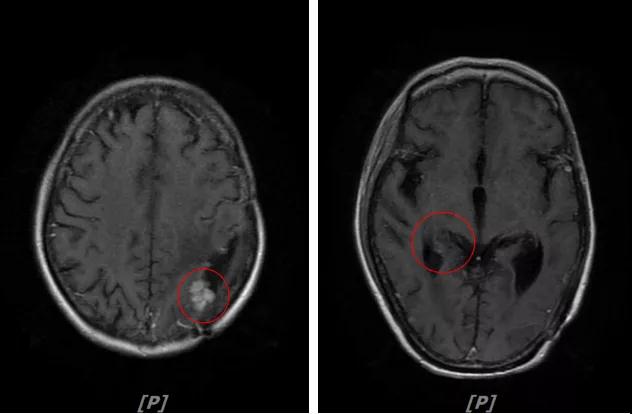

3.病情第2次进展: 2016年12月患者再次出现头痛症状

头颅增强MR:左侧顶枕叶见片状T1WI低信号、T2WI高信号影,增强后病灶边缘见局部斑片状强化改变,邻近脑膜轻度强化改变;右侧脑室三角区内侧见大小约8x14mm的结节影,T1WI低信号、T2WI等高信号,增强明显强化,灶周水肿明显;两侧脑室旁见片状异常信号,T1WI低信号,T2WI高信号,增强未见明显强化,余脑室、脑池、脑沟大小形态可,中线结构居中无移位

左顶叶脑转移瘤术后放疗后,左顶叶术区边缘强化灶;考虑肿瘤复发

右侧脑室三角区内侧转移瘤

两侧脑室旁云絮状异常信号,考虑放疗后改变

患者一线治疗的PFS为37个月。2017年1月,患者二线治疗为在原“拉帕替尼+阿那曲唑”基础上,加曲妥珠单抗治疗。患者头痛症状有所改善,病灶缩小,继续定期复查。